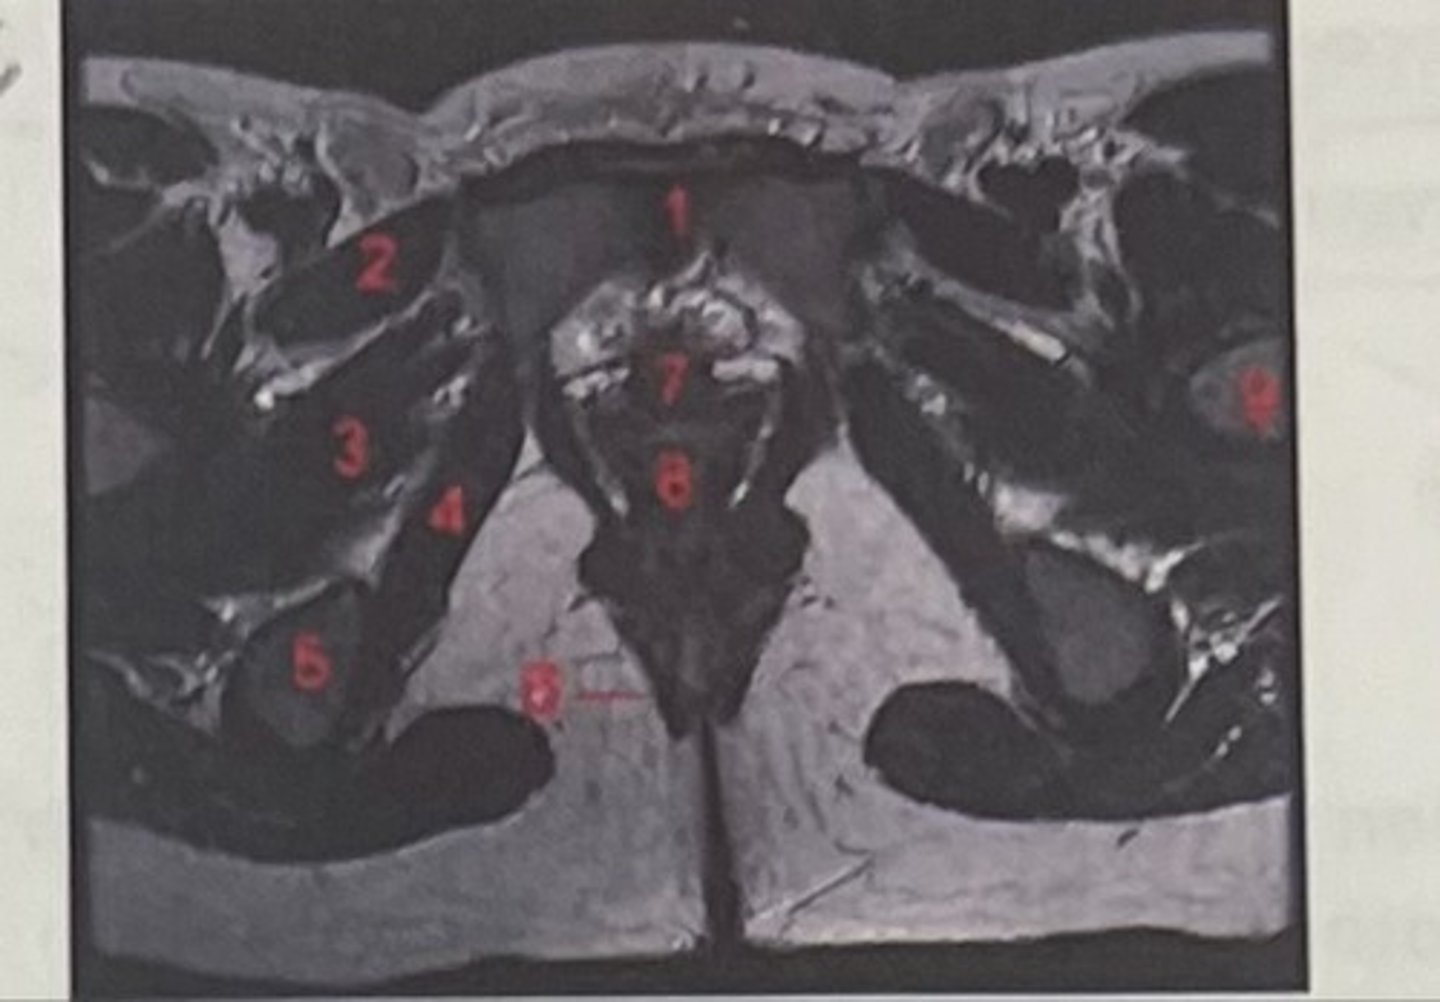

pubic symphysis

What is 1

Pectineus

What is 2

Obturator externus

What is 3

obturator internus

What is 4

ischial tuberosity

What is 5

external spincter

What is 6

Urethra

What is 7

Vagina

What is 8

Femoral nerve

What is 9